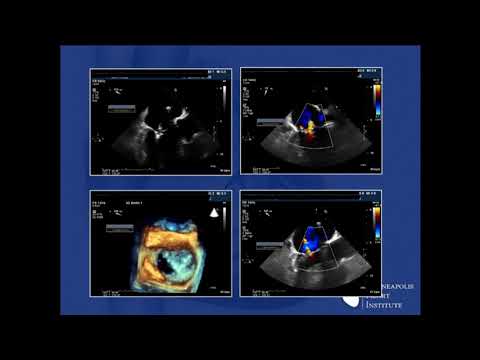

Tendyne Transcatheter MVR: Global Feasibility Results - Paul Sorajja, MD